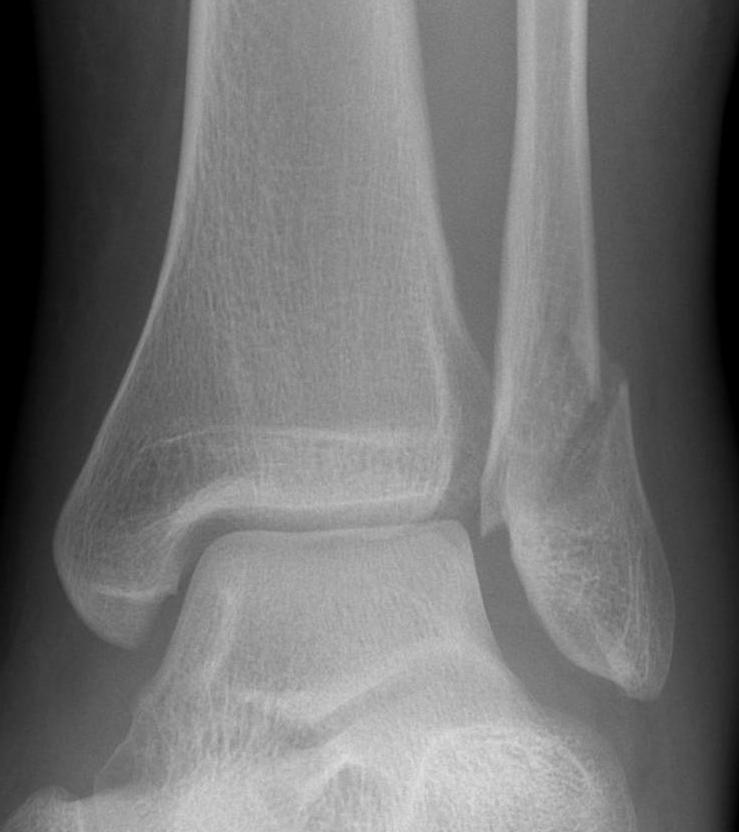

Isolated Weber C fracture

Weber C fracture Weber C fracture with deltoid ligament injury

Maisonneuve injury: proximal fibula with open medial clear space

Definition

Fracture above syndesmosis

Syndesmosis disrupted +/- deltoid ligament

Syndesmotic injury

Xray assessment

| Increased tibio-fibular Clear space | Overlap | Increased medial clear space |

|---|---|---|

|

Medial border of the fibula Lateral border of the posterior tibia (incisura fibularis) Measured 1 cm above the plafond |

Overlap of the fibula and the anterior tibial tubercle | Deltoid ligament injury |

| <5mm AP and mortise |

> 6 mm AP view > 1 mm mortise view |

Maisonneuve / proximal fibular injury |